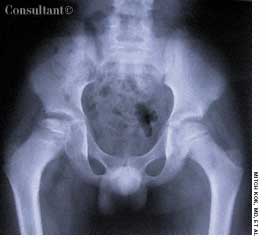

A roentgenogram of the kidneys, ureter, and bladder of a 58-year-old man shows bilateral stones in the renal pelvis and the renal calyces. The patient had a history of recurrent urinary tract infections caused by Proteus mirabilis. A ureteral catheter (pigtail) had been placed in the pelvis of the left kidney to facilitate drainage.